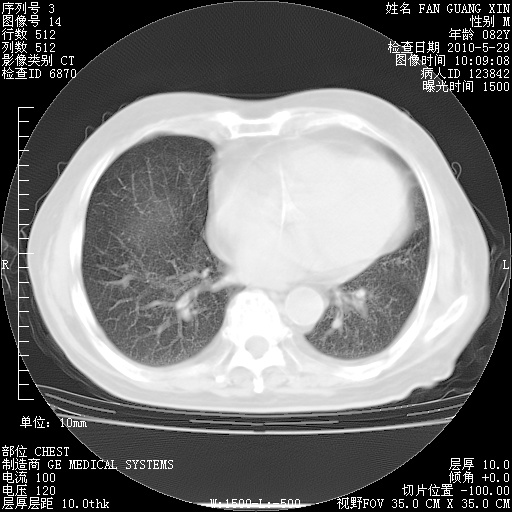

再治疗10天后的肺部CT

阅读此次胸部CT,肺间质渗出性改变较入院时有吸收。目前从体温、白细胞、中性分叶明显增高,肯定存在细菌感染(发生医院感染哦,若无消化道及泌尿系统等感染的依据,肺部感染可能大)。若你院头孢哌酮舒巴坦钠耐药率较高,同意你的方案,若48小时体温仍高,可考虑使用碳青霉稀类抗菌药物,同时可予超声雾化、注意滴数时加大液体量。白蛋白33.30g/L较低哦,需加强营养等支持治疗。